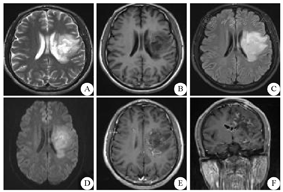

患者 男性,30岁,农民,既往体健,无感染及疫苗接种史。因"右侧肢体无力伴言语不清5个月余,加重8 d"于2018年5月23日入临沂市人民医院。患者于5个月前无明显诱因出现右侧肢体无力伴言语不清,持物不稳,右侧中枢性面瘫,在莒南县人民医院就诊,行头颅MRI平扫显示:左侧额叶、基底节区斑片状长T1长T2信号,弥散加权成像(DWI)显示高信号,诊断:脑梗死?住院期间,患者病情较前无改善,为求进一步诊治,经临沂市人民医院神经外科门诊,以"左侧丘脑恶性肿瘤"收入院。2017年12月21日患者行头颅CT扫描显示左侧基底节区、左侧侧脑室体旁斑片状低密度影(图1),并在全麻状态下行左顶穿刺基底节区病变活检术,征求家属同意后将病理切片送至北京神经外科研究所检验,病理诊断为"炎性脱髓鞘性假瘤",建议激素冲击治疗。当时患者病情较前好转,未同意。2017年12月23日行头颅MRI检查显示左侧额叶、基底节区、侧脑室体旁T2WI、T2液体衰减反转恢复序列(FLAIR)呈高信号;T1WI呈低信号;DWI显示高信号;注入钆喷酸葡胺对比剂后呈不均匀线性强化(图2)。

A~C:平扫;D:DWI;E、F:增强扫描;DWI:弥散加权成像